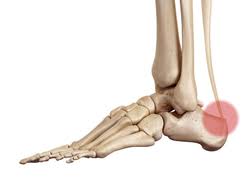

Bei vielen Menschen stellt die Achillesferse daher den neuralgischen Punkt dar. Typisch ist ein Druckschmerz am Ansatz der Achillessehne sowie eine Verdickung Rötung oder Schwellung der Sehne. Diese ziehen an der Achillessehne und verursachen die Schmerzen.

Ein ergänzendes biokinematisches Fusstraining Biokinematik hilft die Ursache Ihrer Achillesschmerzen zu bekämpfen und somit nachhaltig ganz zu gesunden ohne Schmerzen. Typische Symptome einer Achillodynie Reizung der Achillessehne sind zunächst belastungsabhängige Schmerzen meistens einige Zentimeter oberhalb der Ferse midportion Achillodynie sie können jedoch auch direkt am Ansatz der Achillessehne an der Ferse auftreten ansatznahe Achillodynie.

Typisch ist ein Druckschmerz am Ansatz der Achillessehne sowie eine Verdickung Rötung oder Schwellung der Sehne. Wenn ein knöcherner Vorsprung an der Oberkante Ihres Fersenbeins zu einer Reizung der Sehne führt nennt man das Haglund-Exostose. Manche Betroffene klagen insbesondere beim Aufwärmen über Schmerzen. Mit zunehmendem Alter werden durch Verschleiß der Fasern unsere Sehnen schwächer. Ein MRI zeigte eine typische spindelförmige Verdickung der Sehne jedoch keine fortgeschrittene Degeneration der Sehnensubstanz selbst. Bei vielen Menschen stellt die Achillesferse daher den neuralgischen Punkt dar. Besonders durch die Reibung der Strukturen und die Entzündung der sehr empfindlichen Knochenhaut entstehen diese Schmerzen. Die gereizte Achillessehne ruft die Entzündungsreaktion hervor. Die entzündete Achillessehne ihr Ansatz am Fersenbein und das umgebende Gewebe sind gereizt.